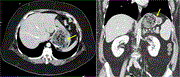

Unique multidisciplinary approach in a patient with small bowel obstruction and chronic mesenteric ischemia

Sally Tan and others

Journal of Surgical Case Reports, Volume 2023, Issue 10, October 2023, rjad577, https://doi.org/10.1093/jscr/rjad577